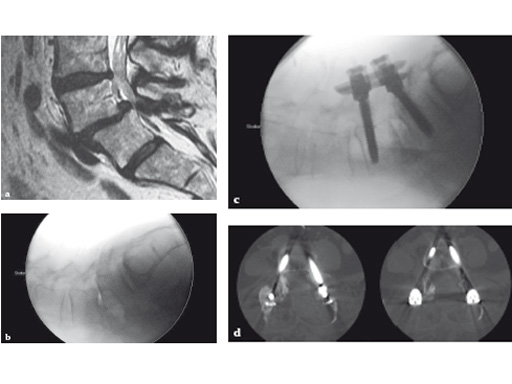

Fig 7ac a Preoperative CT scan: os odontoideum with compression of cervicomedullary junction in a symptomatic patient.

b Intraoperative view of navigated endoscope entering nose. Reference array for navigation has been attached to skull clamp.

c Postoperative CT scan: complete resection of the mass. Patient also underwent occipitocervical instrumentation and fusion.